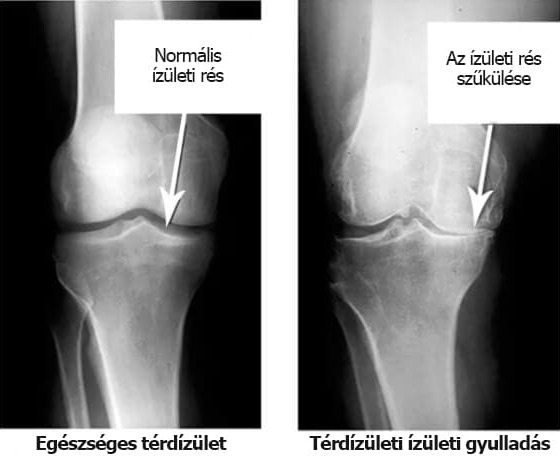

Nézzék meg ezeket a röntgenfelvételeket, és láthatják, hogy a jobb felvételen nincs ízületi üreg, a csontok egymáshoz dörzsölődnek, súlyos fájdalmat okozva. Nagyon nehéz megállítani ezt a folyamatot!